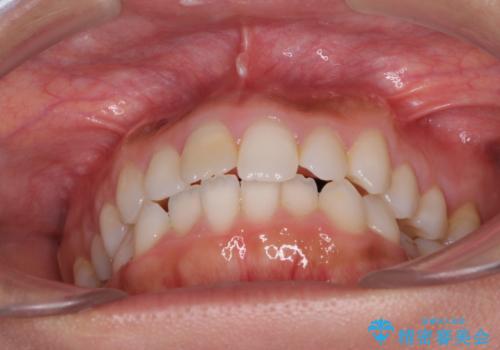

- 上下の前歯のデコボコと奥歯の反対咬合を気にして来院された患者様です。

インビザラインを用い、上下顎ともにIPR(歯と歯の間を削る)により叢生を改善することとしました。

奥歯の反対咬合は、骨格に由来するものであるため、改善できるところまで改善していくこととしました。

治療を長期化させたくないとのご要望があったので、左下の90度捻転した歯は、捻転した状態のゴールとしました。